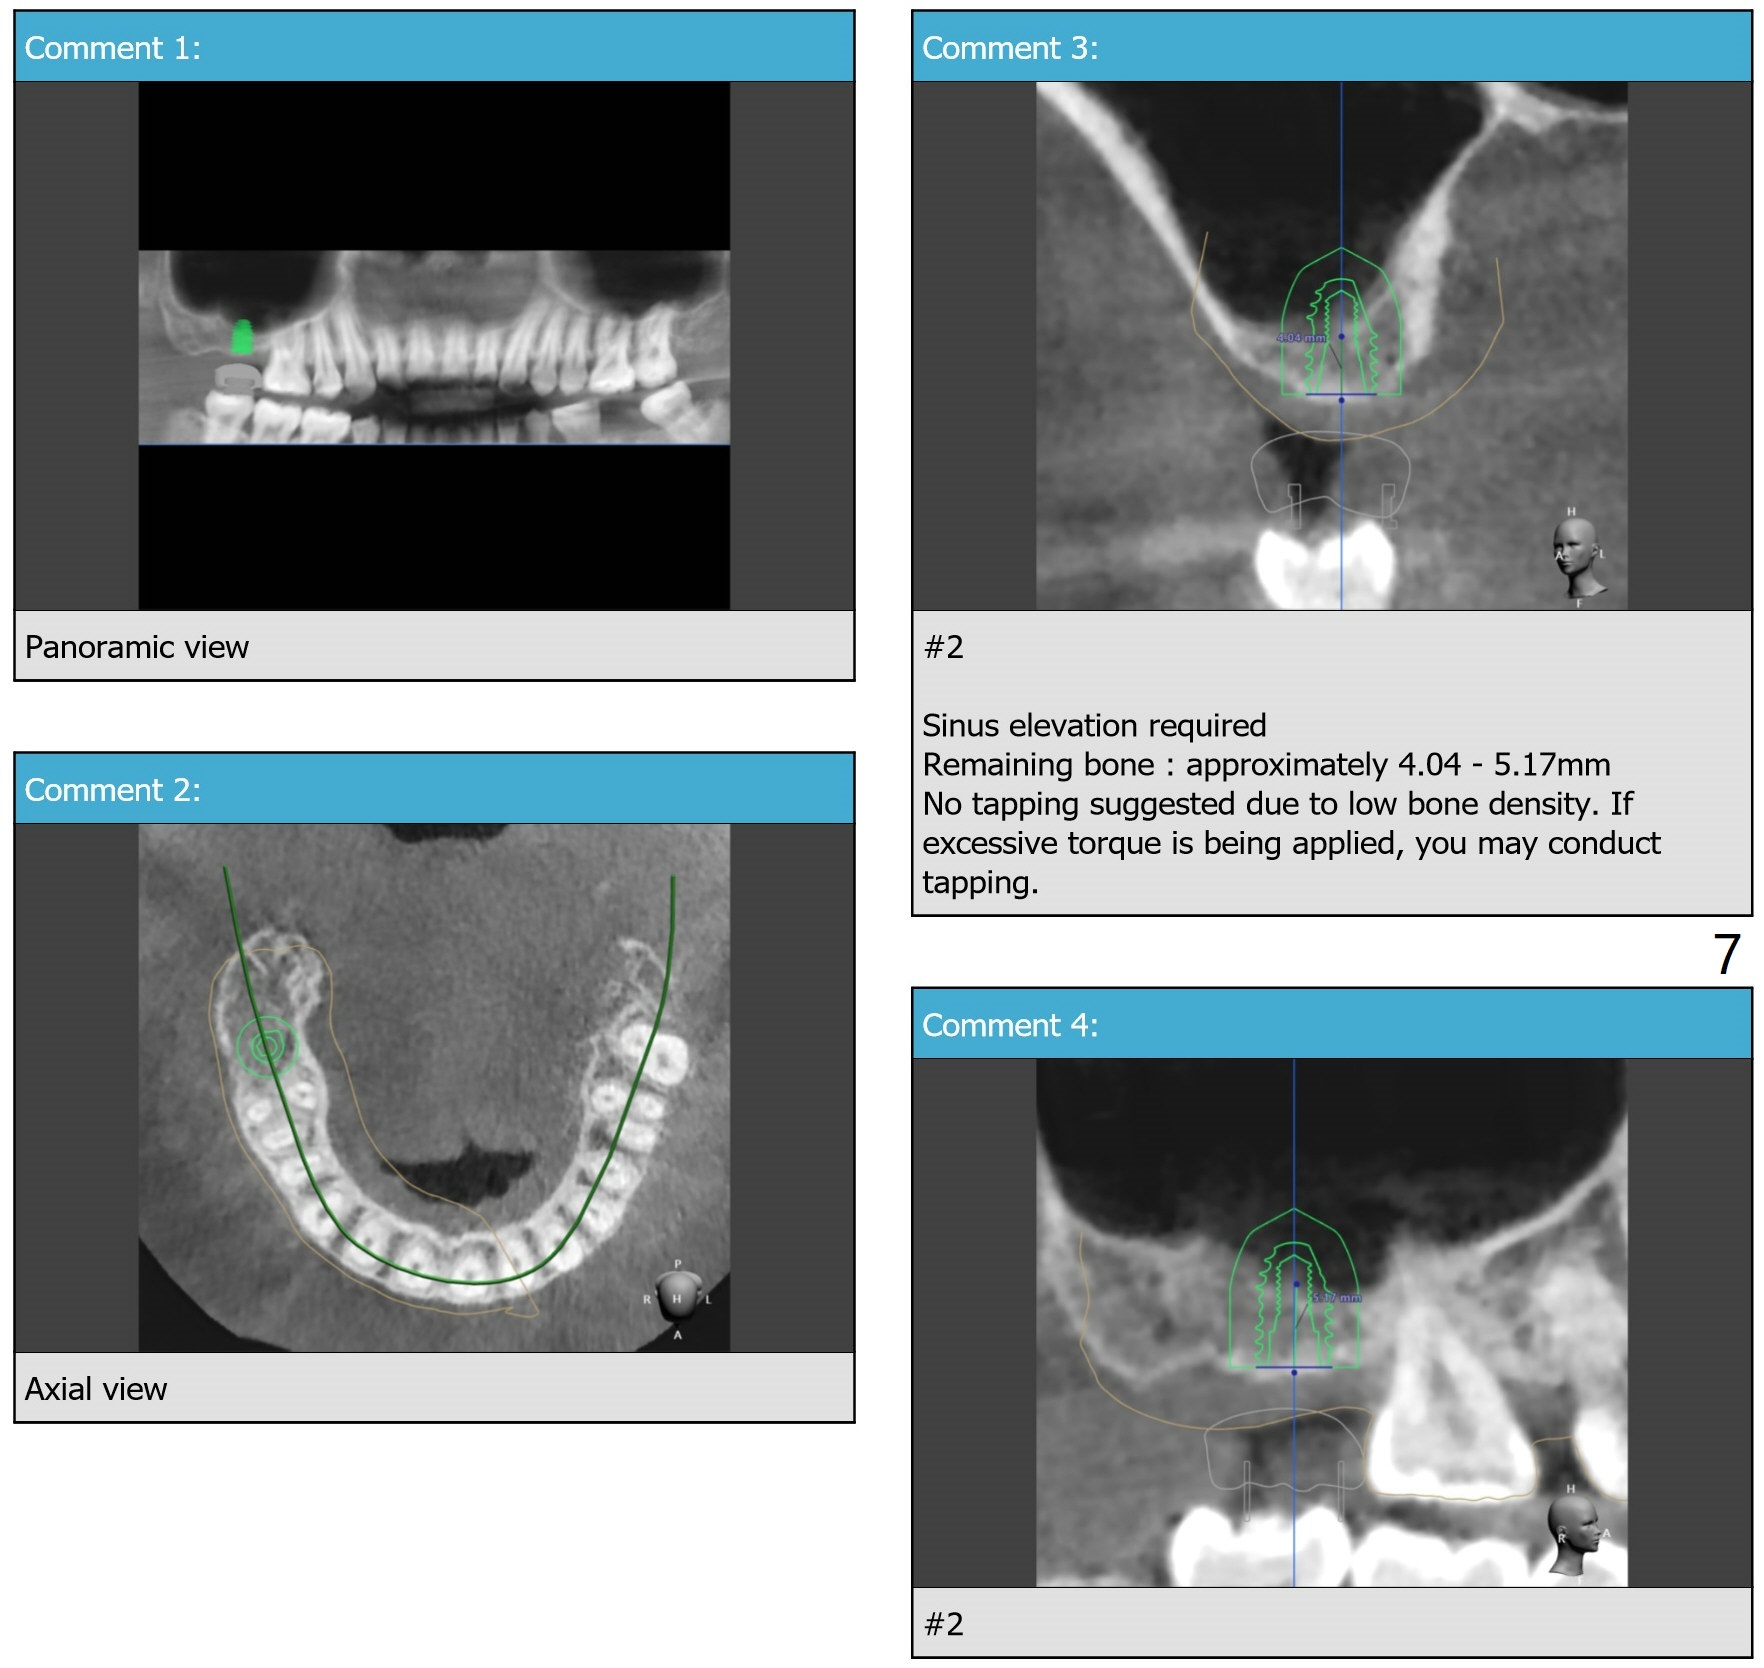

A 25-year-old woman. For sinus lift, 9 mm offset will be used from now on so that DIO sinus approach kit can be applied. Get ready water lift.

Lower Molar

Immediate Implant,

Trajectory II